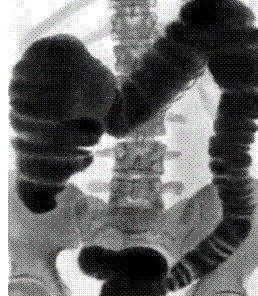

Ирригоскопия – это рентгенологическое исследование толстой кишки с помощью двойного контрастирования. В качестве контрастного вещества используется барий, который вводится с помощью клизмы.

Процедура позволяет тщательно изучить состояние восходящего отдела толстой кишки, нисходящего отдела и прямой кишки, а также некоторые отделы тонкого кишечника и слепой отросток (аппендикс).